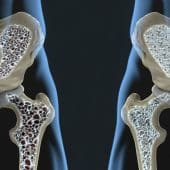

Ученые, возможно, нашли способ, помогающий организму восстановить собственные кости. Важную роль в методе играет рецептор GPR133. Такая терапия может в перспективе изменить подход к лечению остеопороза.